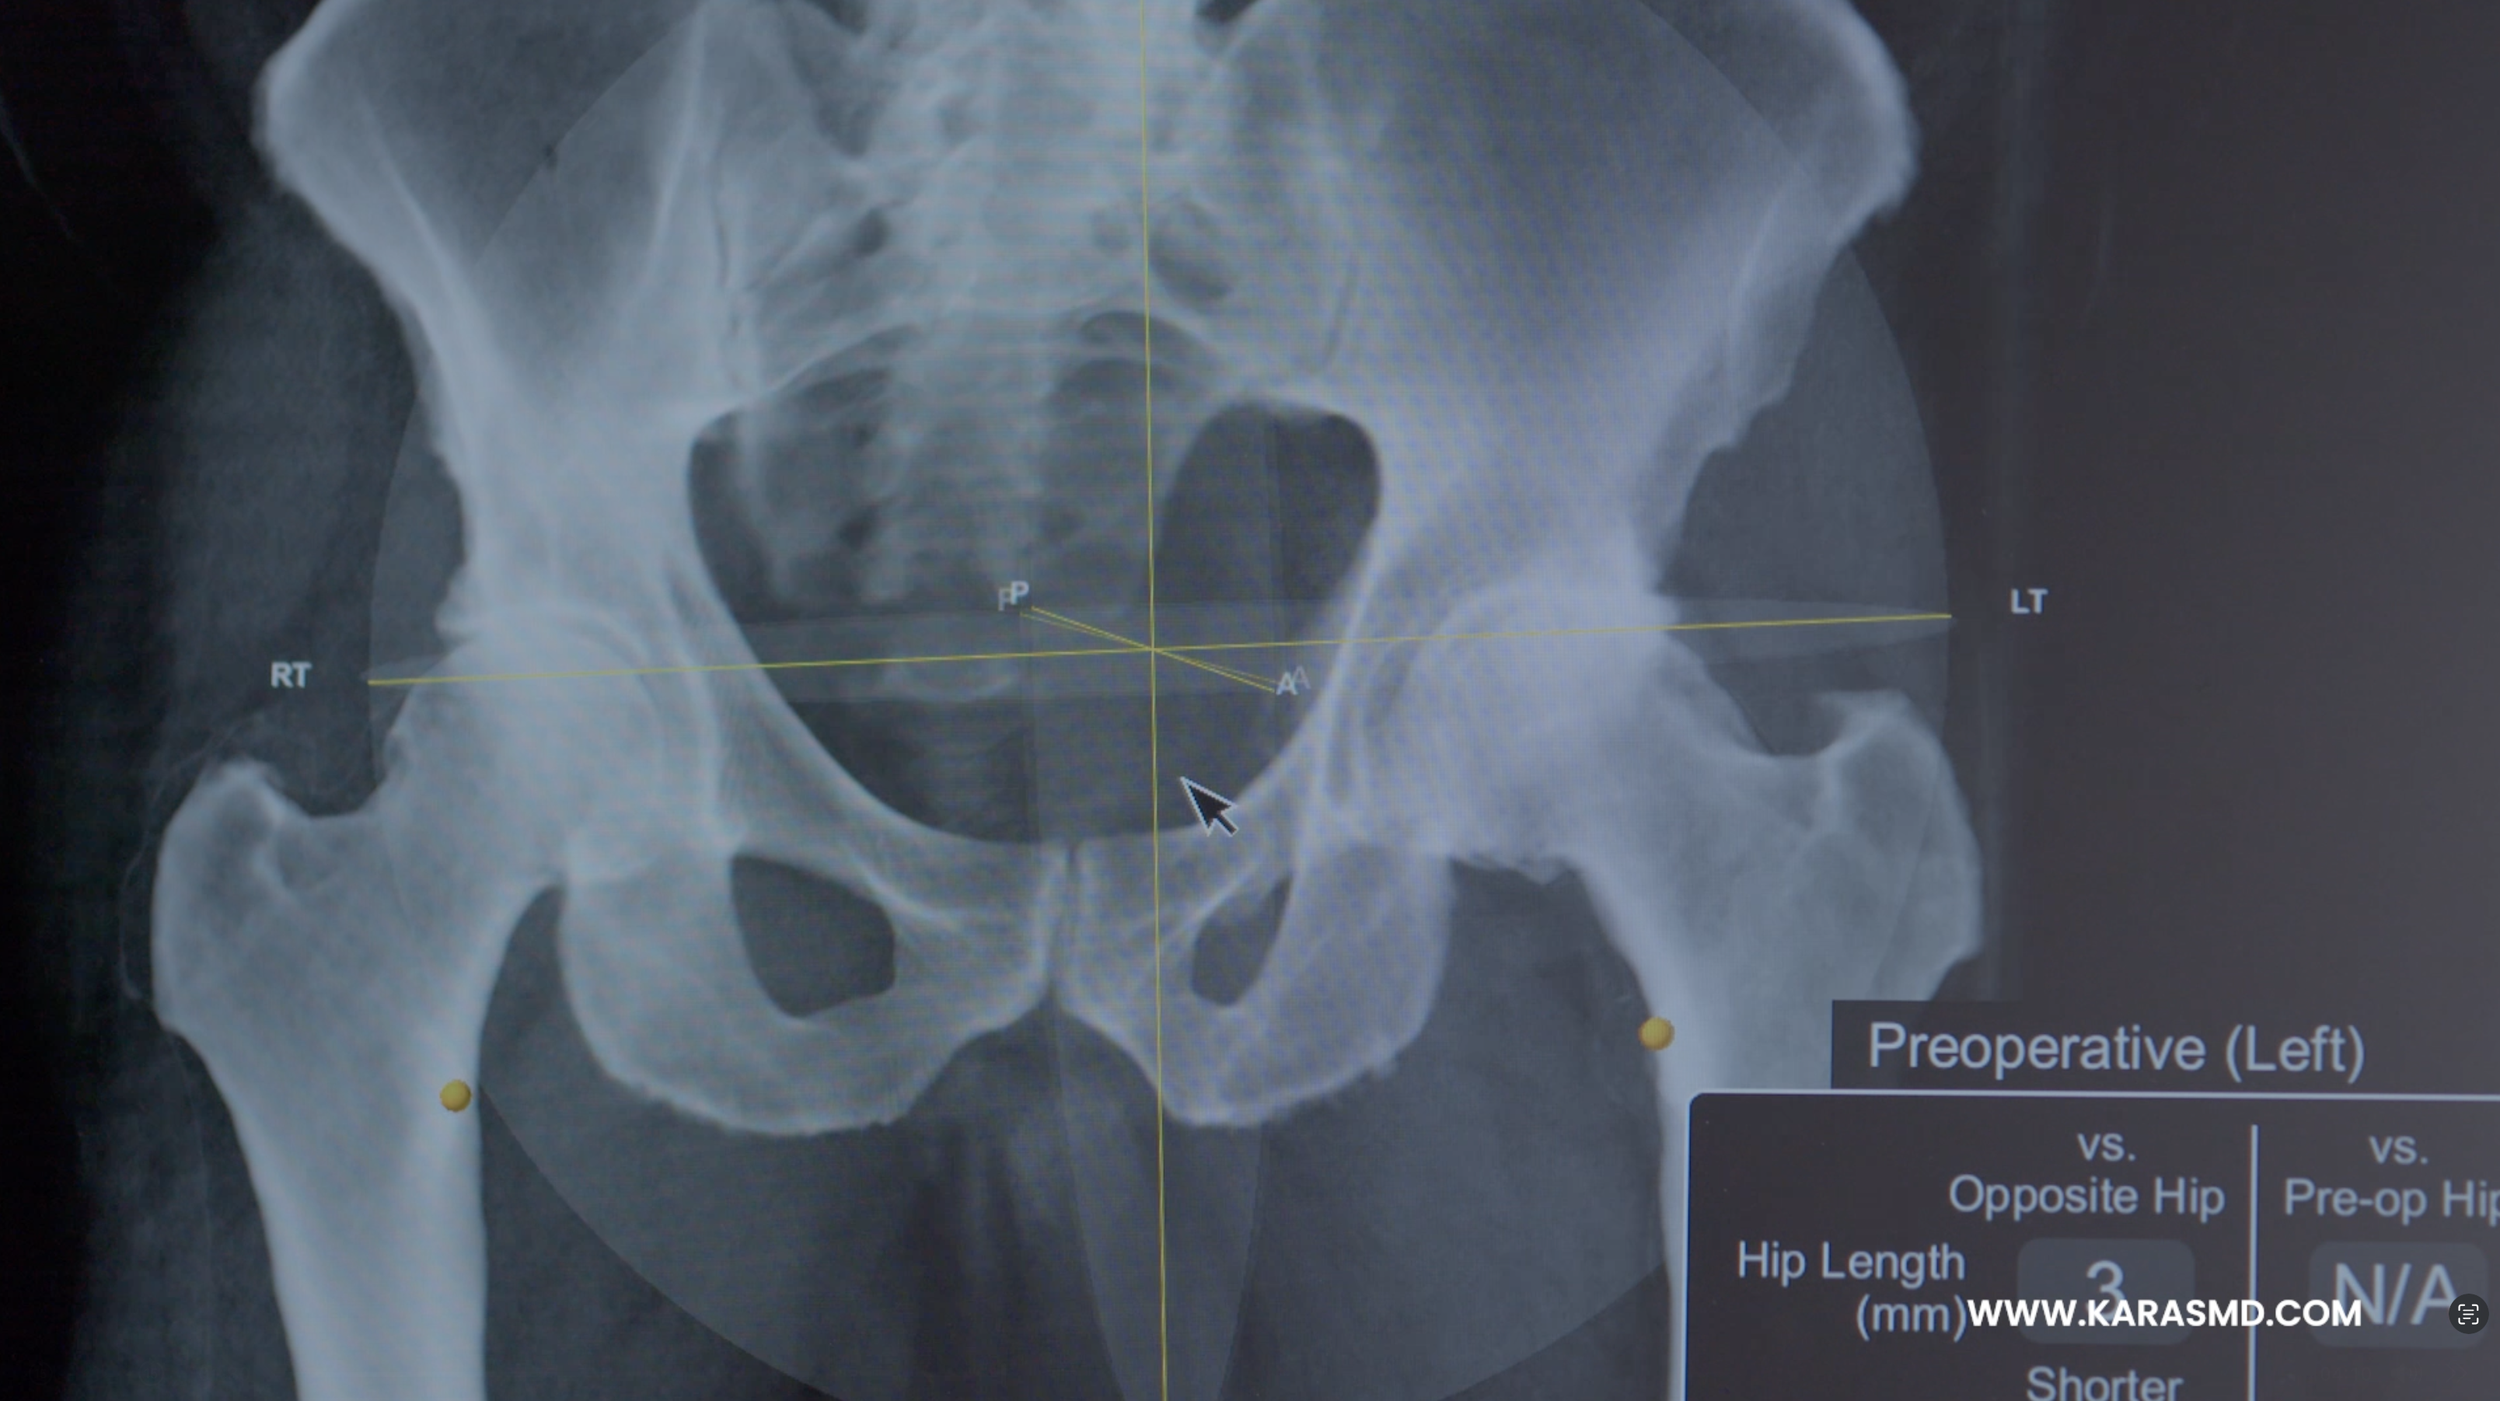

Dr. Karas ‘Toms Story’

“It’s been six months since my hip replacement… and I’m back to doing all the things I love.” That line sets the tone for this heartfelt patient story created for Dr. Karas, who came to us with a vision: to create more than just a standard testimonial, but something cinematic and inspiring, something that could encourage others to take their first step.

Told through the words of Tom O’Grady, a patient-turned-advocate with no on-camera experience, this piece was crafted to feel more like a short film than a traditional medical video, capturing not just the outcome, but his transformation.